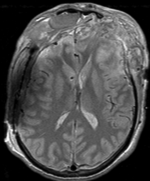

Within Exam:

Exam 1 PD aligned to T1

Exam 1 GRE aligned to T1

Exam 1 DWI aligned to T1